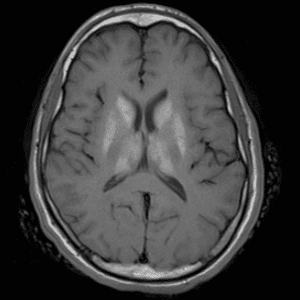

Neurodegenerative Diseases